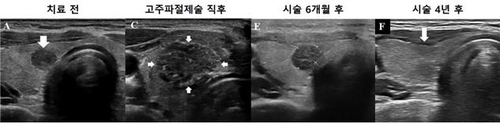

이 중 종양 크기가 1㎝ 이하인 미세 갑상선유두암에 시술한 고주파절제술의 효과와 안전성이 확인됐다는 연구결과가 나왔습니다.

고주파절제술은 미세한 바늘을 삽입한 뒤 고열로 종양과 주변 조직을 괴사시키는 치료법으로, 괴사한 조직은 시간이 지나면 자연스럽게 사라집니다.

이번 연구에서 고주파절제술로 괴사한 종양 조직은 점점 줄어들어 마지막 시점에는 전체 환자의 95.9%에서 완전히 사라졌습니다.